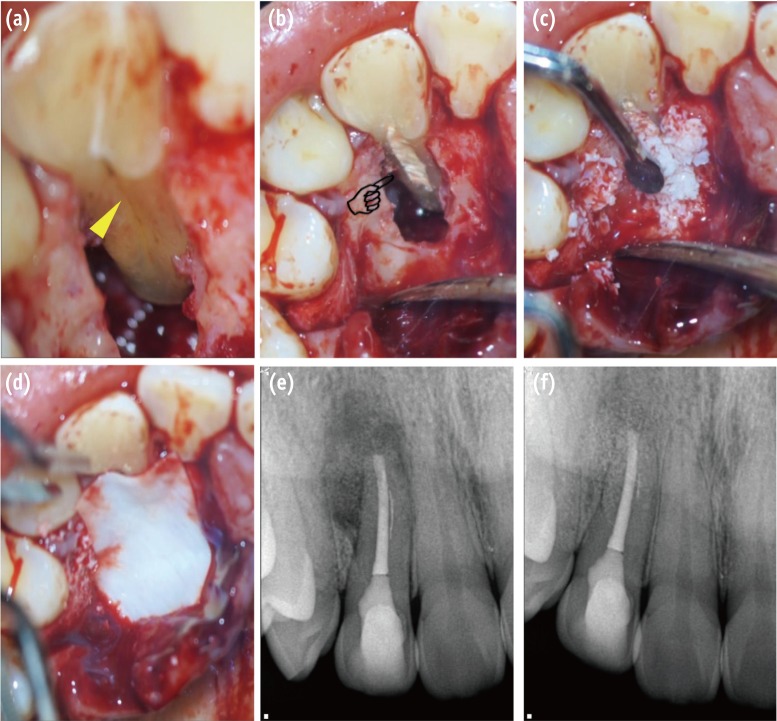

Recently, calcium silicate-based cements showing excellent biocompatible characteristics have been developed for the dental field. In several case reports, MTA has been used to restore the subgingival groove of a tooth. Although MTA has several favorable properties (excellent biocompatibility, sealing ability, and ability to set in moisture), difficulty in material handling and the possibility of wash-off, especially in a transgingival defect with a long setting time, make it difficult to use in PGG cases.35 Because PGG is mostly distributed from the crown area to the root of the tooth, mechanical properties that can endure intraoral conditions and biocompatibility with subgingival conditions are very important considerations. Some authors have reported a successful treatment outcome for PGG with Biodentine, describing advantages such as easy handling, a relatively short setting time of 9 to 12 minutes, improved mechanical properties, good biocompatibility, and regenerative potential (Figure 2b).2,55,56

Attam et al. reported that a combined technique of bone graft and membrane significantly reduced the pocket depth compared with cases treated by open flap debridement (Figures 2c and 2d).35 Anderegg et al. also reported 10 cases of successful treatment after 6 month follow-up using a polytetrafluoroethylene membrane.57

Figure 2

Surgical procedure for management of PGG-related periradicular pathosis. (a) PGG is verified along the root surface to the region of the apical third (yellow triangle); (b) The PGG was filled with Biodentine after saucerization (pointing finger); (c) The bony defect was filled with artificial bone graft material; (d) The bone-filled lesion was covered by an absorbable membrane; (e) Post-operative radiograph; (f) 8 month follow-up radiograph reveals healing of the periradicular lesion. PGG, palatogingival groove.

Figure 2 Surgical procedure for management of PGG-related periradicular pathosis. (a) PGG is verified along the root surface to the region of the apical third (yellow triangle); (b) The PGG was filled with Biodentine after saucerization (pointing finger); (c) The bony defect was filled with artificial bone graft material; (d) The bone-filled lesion was covered by an absorbable membrane; (e) Post-operative radiograph; (f) 8 month follow-up radiograph reveals healing of the periradicular lesion. PGG, palatogingival groove.